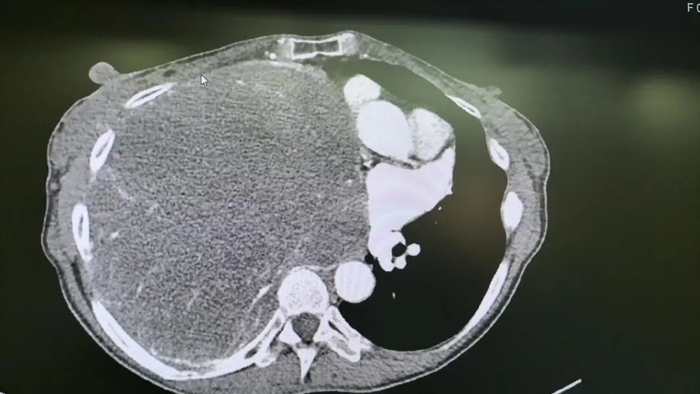

增强CT的结果让医生也大吃一惊——肿瘤直径已经超过20公分,占满她的整个右侧胸腔,甚至蔓延到了对侧胸腔,同时还挤压着肺脏、心脏、纵膈等重要器官。由于肿瘤实在太大,通过CT根本无法判断肿瘤是从哪里生长出来的。